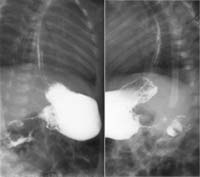

При резко выраженном сужении привратника в результате перильстатики желудка контрастное вещество заполняет только начальную часть пилорического канала, не проникая в двенадцатиперстную кишку — «симптом антропилорического клюва». Вследствие усиленных сокращений желудка и выраженного сужения привратника «клюв» то появляется, то исчезает. Периодическое возникновение этого признака указывает не только на резко выраженный стеноз, но и на присоединившийся к нему стойкий пилороспазм. В основании «клюва» стенка желудка нависает над суженым пилорическим каналом, происходит своего рода инвагинация утолщенного привратника в просвет антрального отдела — «симптом плечиков», или «фигурной скобки» (Рис. 1).

[Увеличить]

Рис. 1. Больной А., 1 мес. Врожденный пилоростеноз. Симптомы «плечиков» и «антрального клюва».